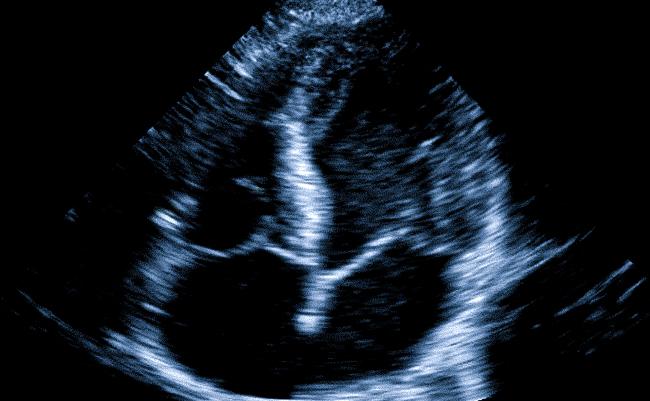

Эхокардиография представляет собой диагностическую процедуру, в которой используются импульсные ультразвуковые волны для исследования состояния сердца. Она назначается при наличии любых проблем с сердечно-сосудистой системой и даже при некоторых других заболеваниях.

Принцип работы данного метода заключается в регистрации ультразвуковых волн, отражающихся от различных структур сердца и сосудов, по результатам которых создается изображение на мониторе. Опытный специалист способен, изменяя положение датчика и его угол наклона, детально проанализировать структуры сердца и получить точные данные о его функционировании.

- Двухмерная. В этом случае датчик показывает двухмерное изображение на экране.